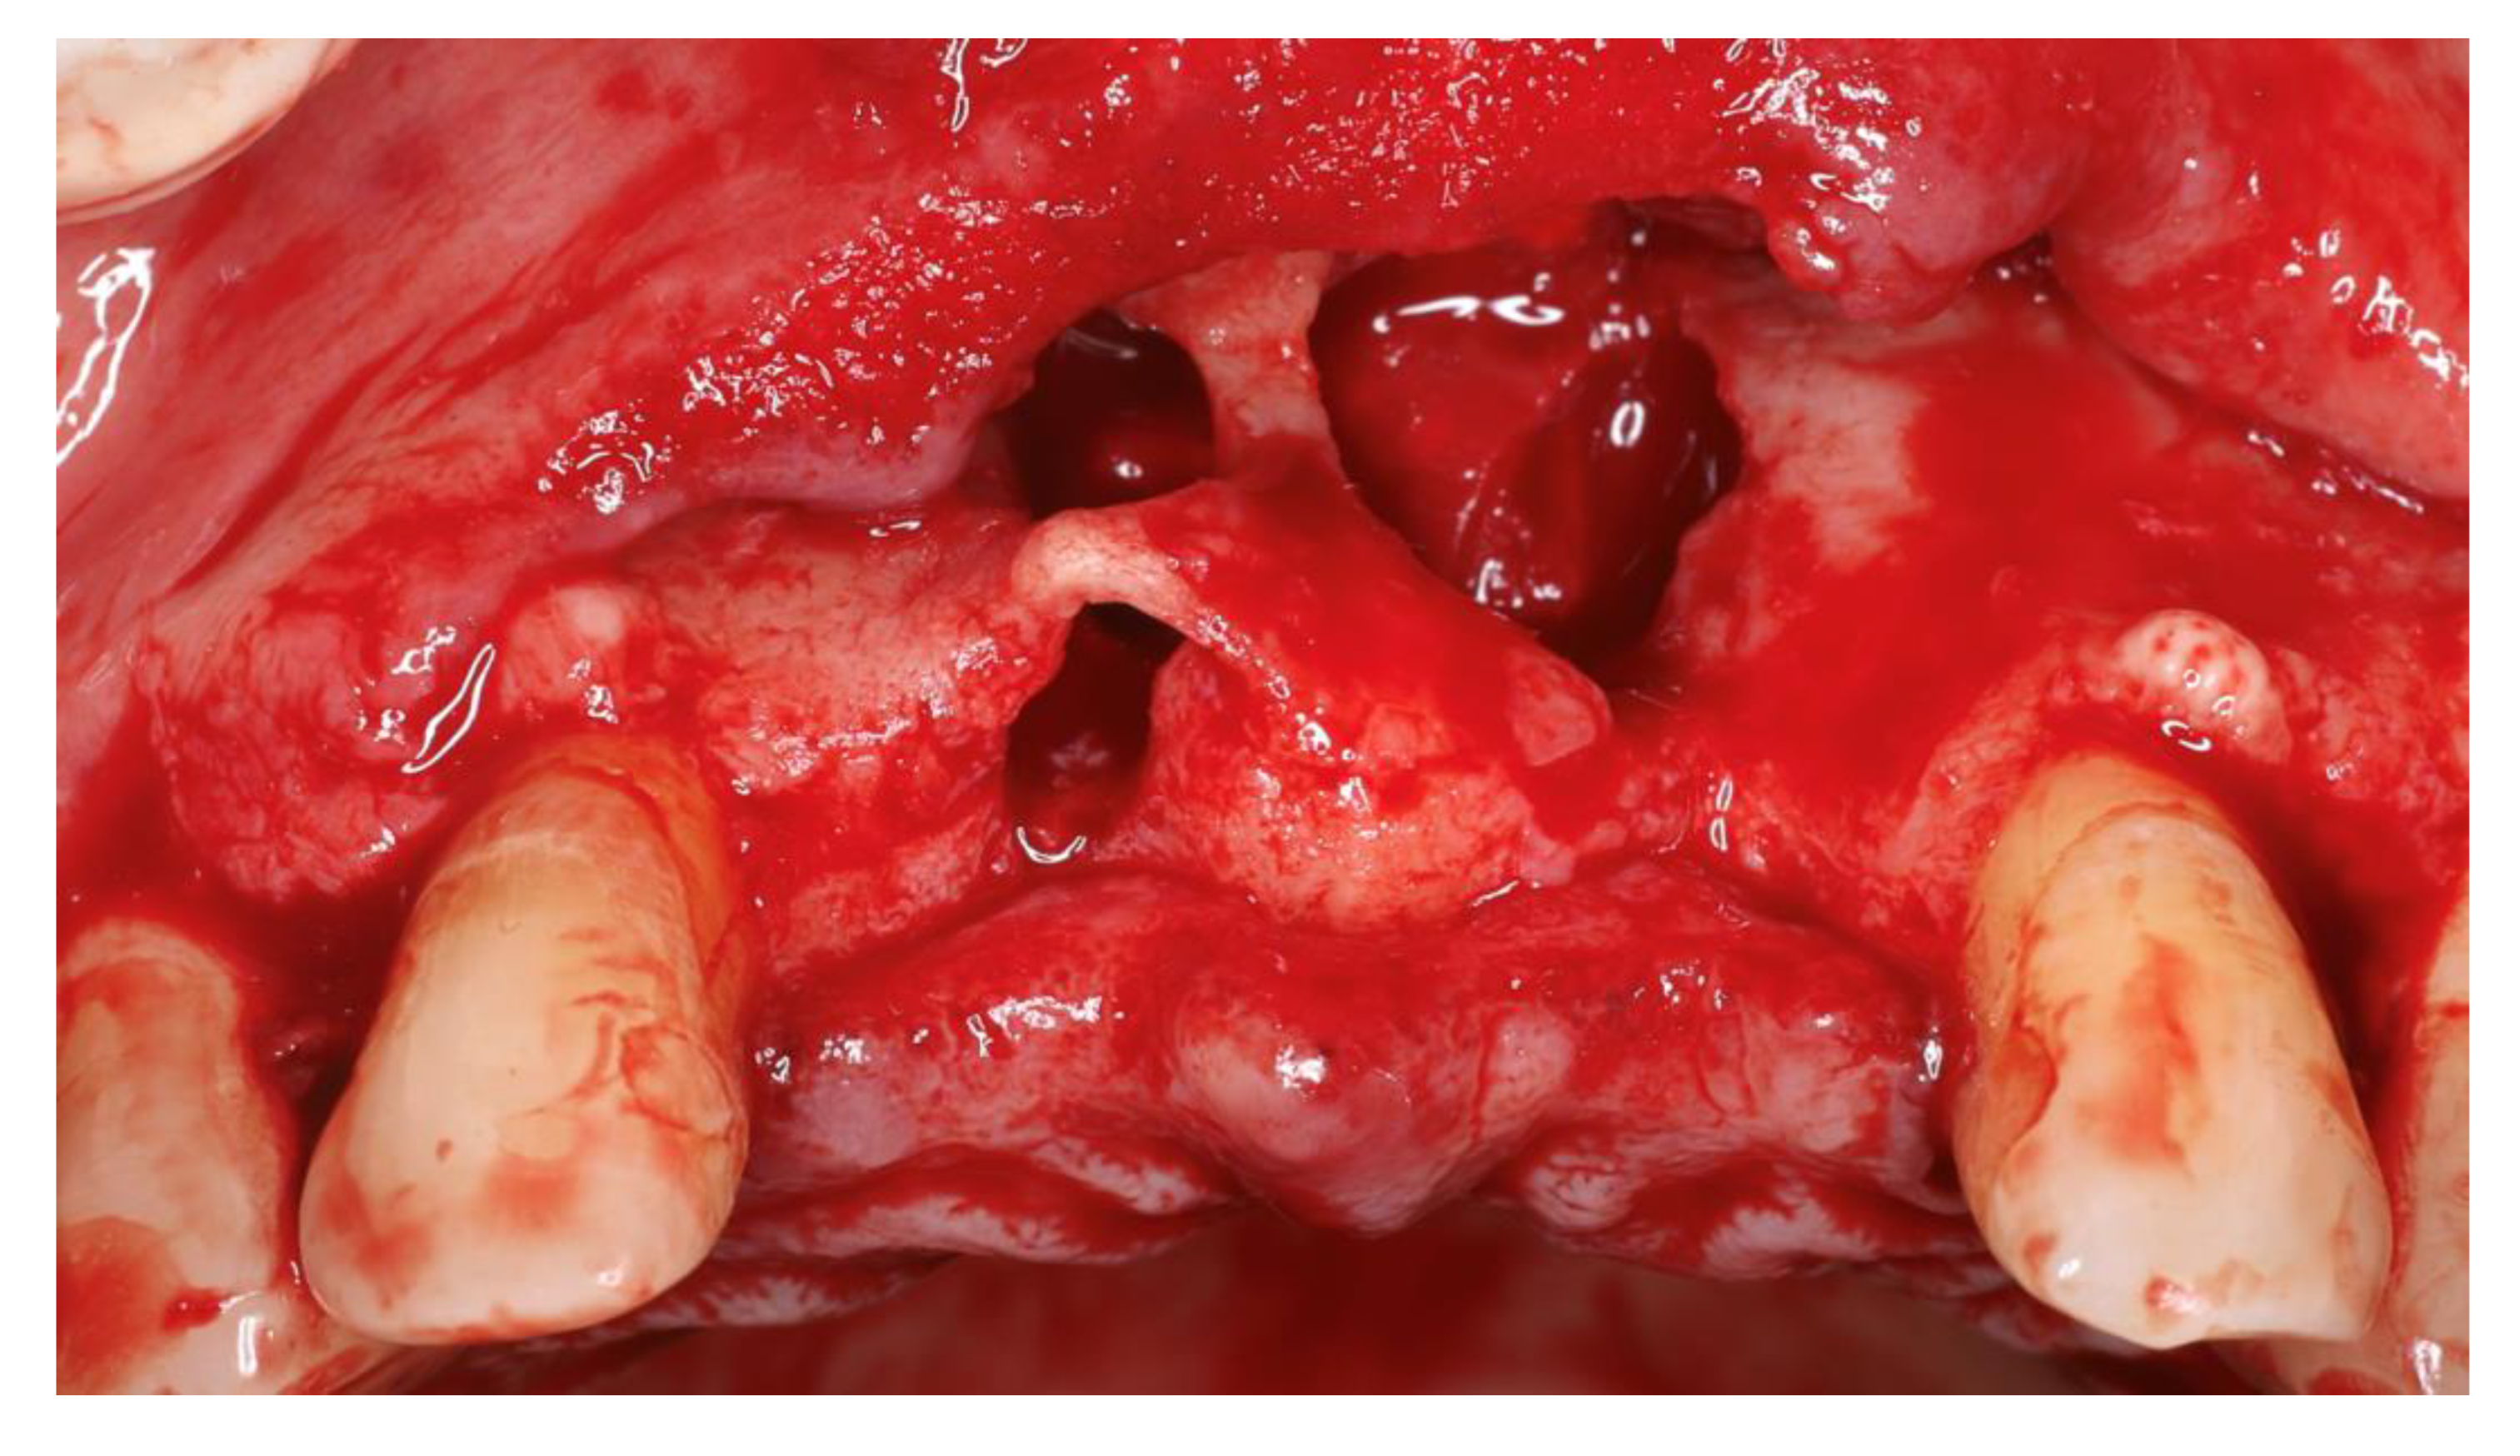

Figure 4. Different view after cyst enucleation.

Local anesthesia with articaine (artinibsa® 40mg/ml + 0.01mg/ml, Inibsa®, Spain) was given. A linear incision with a 15 blade was performed form the distal aspect of tooth 13 to mesial of tooth 23 where a releasing incision that cross the mucogingival line was performed. A full thickness flap was elevated, and the cyst was enucleated (Figure 4). During odontogenic of the cyst enucleation (histological established), special attention was given to maintain the integrity of the anterior nasal spine. Even with the carfule enucleation, a communication with the nasal floor occurred and a loss of the palatine bone plate was observed (Figure 4).